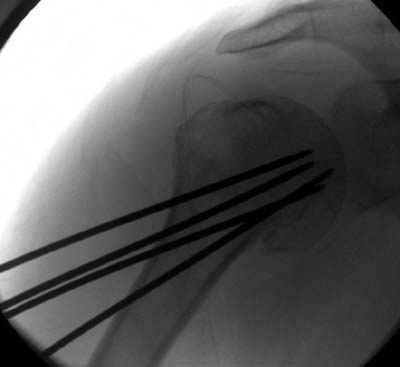

Уважаемые коллеги

сделать закрытую репозицию с помощью ЭОПа совсем не сложно, после этого еще проще провести 3-6 спиц и получить красивую рентгенограмму. Есть только небольшая проблема это ROTATOR CUFF. Для плечевого сустава только костное восстановление не достаточно. для функции плечевого сустава нужны вращатели.

Давайте представим себе состояние манжетки вращателей после вывиха плеча, а еще и с отрывным переломом бугров. Головка может и прирастет, еесли не будет аваскулярного некроза, но хорошего функционального результата не ждите.

Висеть будет красиво. У людей физически активного периода жизни нужно открыть, восстановить костную анатомию и восстановить сухожильный аппарат.

В этом плане Locking plate очень хороша так как позволяет начать движения сразу после операции.

Клинические снимки - 3 недели после операции

с уважением М. Беренштейн